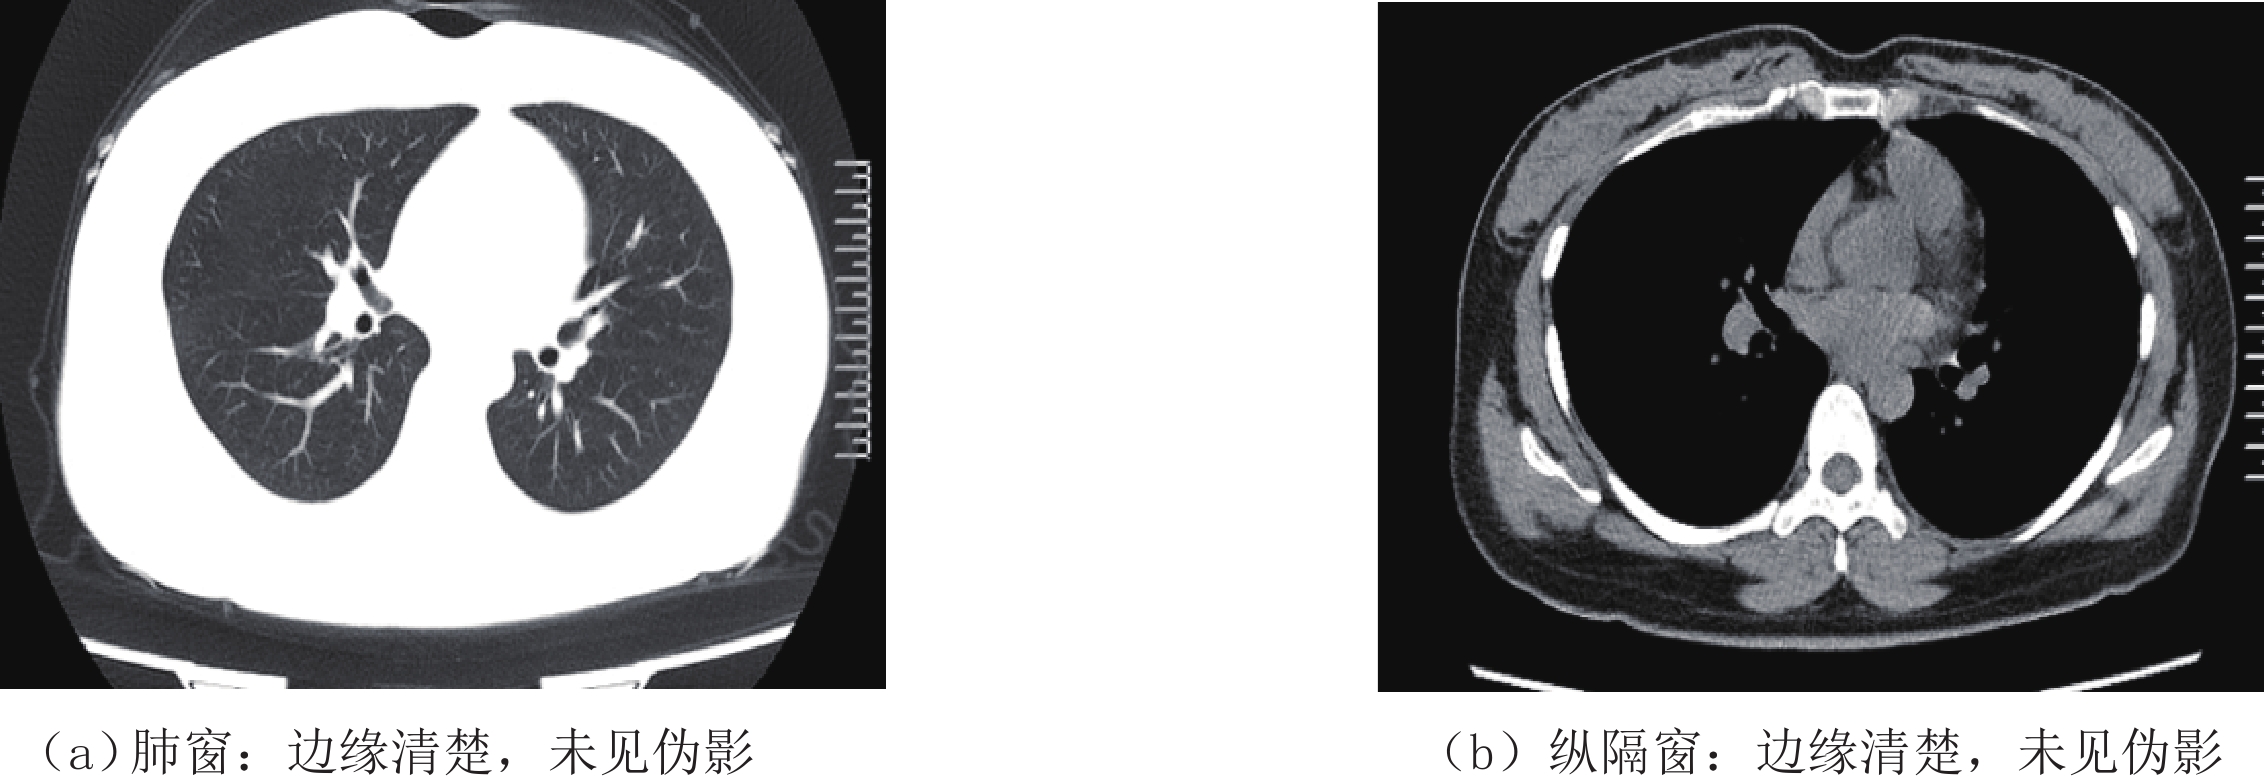

等级 图像质量 0分 未能显示正常结构 1分 大量伪影,正常结构中断 2分 边缘模糊,可见中等量伪影 3分 边缘稍模糊,可见少量伪影 4分 边缘稍模糊,未见伪影 5分 边缘清楚,未见伪影 表 2 两组CTDIvol、DLP、ED比较

分组 主观评分 平均值 统计检验 5分 4分 3分 2分 1分 Z P 低剂量组 16(17.6%) 71(78.0%) 4(4.4%) 0 0 4.13±0.45 -0.963 0.336 常规剂量组 21(23.1%) 67(73.6%) 3(3.3%) 0 0 4.20±0.48 表 4 两组间客观评价结果